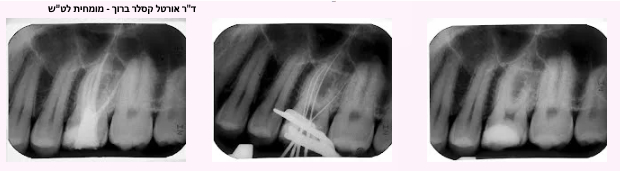

ד"ר אורטל קסלר-ברוך - מומחית לטיפולי שורש (אנדודונטיה)

• בשתי הדוגמאות הנ"ל גם אם אין כאבים והשן קיבלה כתר איכותי, הרי שמראש טיפול השורש למעשה נכשל, ולאחר זמן מה יצוצו שוב הכאבים והדלקת. ברבות הזמן חיידקים אלו שוב יתרבו וישגשגו, והזיהום שייצרו יתפשט אל קצה השורש ומעבר אליו – לעצם ולרקמות שסביב השורש. בצילום הרנטגן נראה איזור כהה, מוצלל, סביב שורש השן, שמעיד על הדלקת. במילים אחרות – כישלון של טיפול השורש.

דוגמא לטיפול שורש במיקרוסקופ בשן טוחנת עם אנטומיה חריגה - 6 תעלות שורש

דוגמא לאפיסקטומי

(טיפול אנדודונטי כירורגי לקיטום חוד שורש דלקתי) ולסתימה רטרוגרדית

מכשיר אלקטרוני שנותן הדמייה של תעלת השורש ושל המיכשור הנמצא בתוכה, ומכוון את הרופא והמיכשור בתוך תעלות השורש. מאפשר דיוק מירבי בעבודה עד קצה התעלה, דבר המחסל שאריות חיידקים גם בקצה המרוחק של התעלה, וחוסך צילומי רנטגן רבים שנועדו לוידוא המיקום המדוייק.

במרפאה מותקן סורק רנטגני דיגיטלי חדיש שמאפשר לאבחנה מדוייקת ומהירה, עם שימוש בקרינת רנטגן מופחתת: קיצור משמעותי באבחנה של צילומי הרנטגן, מדידה אלקטרונית של אורכים שונים, השוואה בין מצבים שלפני טיפול ואחריו ועוד.